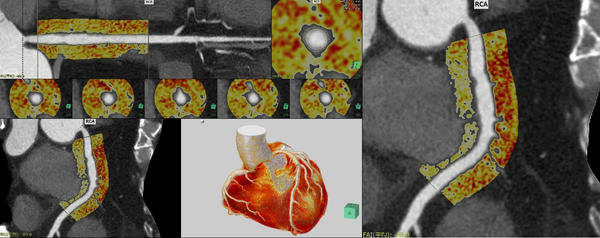

(3)循環器領域の機能アップデート

心臓の動きを補完してより滑らかな4D画像表現を行うことができる「心臓4Dビューア」を新たにラインアップする。非剛体位置合わせの補完技術により,拍動する心臓の4DCT画像から滑らかな4D画像表現が可能。また,冠動脈解析(CT)内の機能として,血管周囲の炎症の指標として近年関心が高まっている冠動脈脂肪組織濃度(FAI)の計測機能*5を追加する。循環器領域のご要望に応える機能を搭載し,医療の質向上に貢献する。

FAIの解析画面